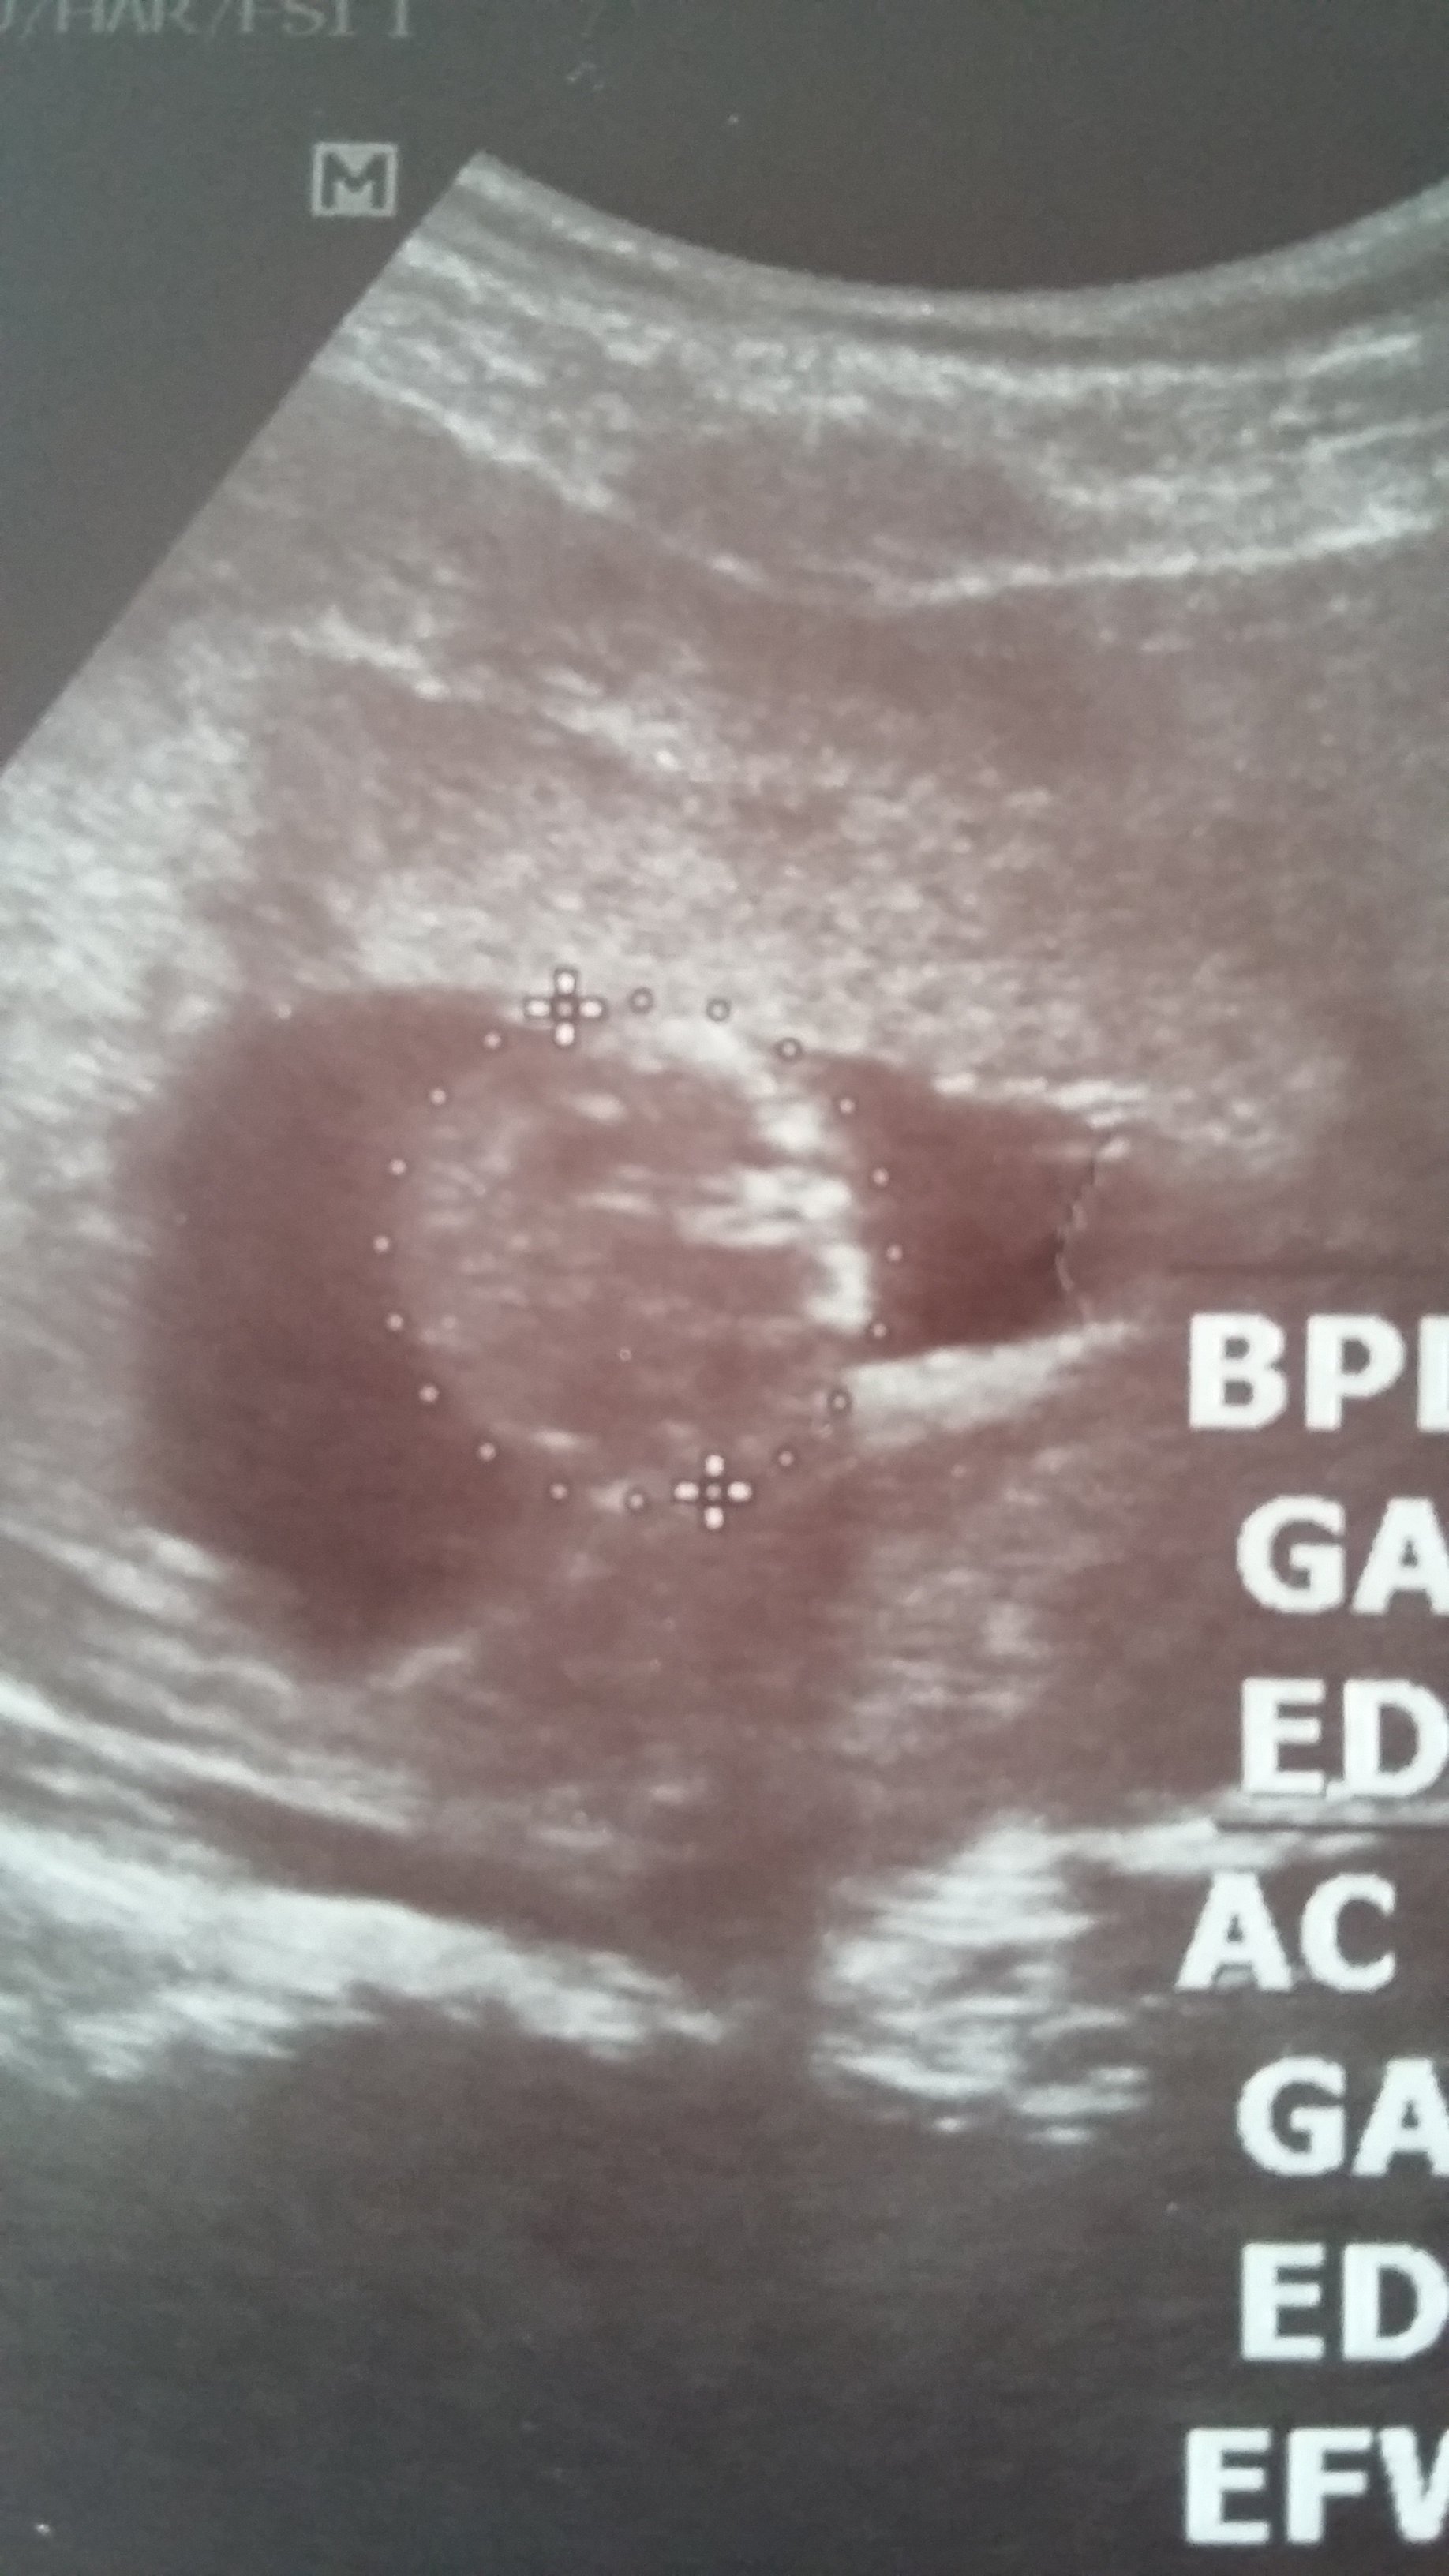

To na dzień dobry mój bobas przesyła uśmiech :)

1467097338169-1486186345.jpg

• 1467097338169-1486186345.jpg